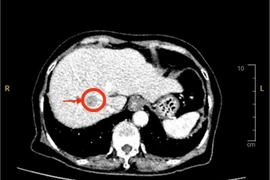

Đau nhẹ vùng thượng vị, đi khám phát hiện u gan phức tạp

Ung thư gan phát hiện sớm có thể điều trị khỏi bằng phẫu thuật hoặc can thiệp. Khi u lớn hoặc xâm lấn mạch máu, việc điều trị sẽ rất khó khăn, tiên lượng xấu.